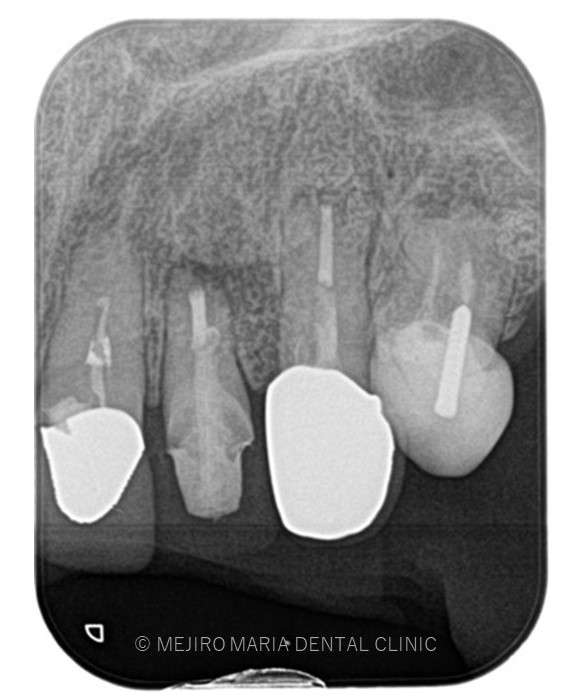

でのリカバリー_治療前感染した人工骨が確認できるレントゲン画像.jpg)

でのリカバリー_治療前、感染した人工骨部分レントゲン画像.jpg)

今回の症例は、他院にて歯根端切除術を行った根尖部(歯の根の先)に充填された人工骨の感染が原因と考えられます。